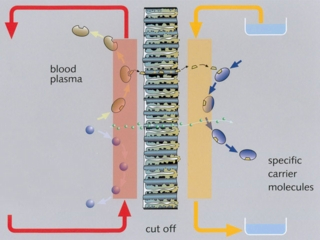

Conventional continuous veno-venous hemodiafiltration is effective in the removal of water-soluble toxins only. In order to clear the blood of albumin-bound, hydrophobic substances, additional adsorber or acceptor substances are necessary to enhance mass exchange.

Aim is the development of an efficient and economic artificial liver support concept based on the transmembranous elimination of toxins relevant in liver failure with alternative synthetic substances – the nanosorbents. In a disposable ad-on for standard renal replacement therapy units, the patient’s blood flows through a circuit with an optimised hollow fiber hemodiafilter. The other side of this membrane is cleansed with a nanosorbent solution in counter-directional flow, which is discarded after passing the filter. A screening platform (1:30 and 1:125 in vitro model) has been developed for evaluating nanosorbents considering the complex dynamic interactions of adsorber substances, dialysis fluid dynamics, and hollow fiber specifications with human blood or plasma.

Aim is the development of an efficient and economic artificial liver support concept based on the transmembranous elimination of toxins relevant in liver failure with alternative synthetic substances – the nanosorbents. In a disposable ad-on for standard renal replacement therapy units, the patient’s blood flows through a circuit with an optimised hollow fiber hemodiafilter. The other side of this membrane is cleansed with a nanosorbent solution in counter-directional flow, which is discarded after passing the filter. A screening platform (1:30 and 1:125 in vitro model) has been developed for evaluating nanosorbents considering the complex dynamic interactions of adsorber substances, dialysis fluid dynamics, and hollow fiber specifications with human blood or plasma.